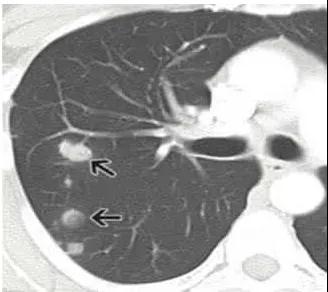

肺部結(jié)節(jié)是指在胸部影像學(xué)檢查中發(fā)現(xiàn)的直徑小于3厘米的球形病灶。肺部小結(jié)節(jié)是指直徑小于1厘米的球形病灶。

比如錯構(gòu)瘤、血管瘤等良性的腫瘤,也可以表現(xiàn)為肺結(jié)節(jié)。

錯構(gòu)瘤可以理解為長錯了地方的正常組織,比如一些軟骨成分長在了肺里面,這與先天發(fā)育有關(guān)。

如果體積大于1厘米,而且這個結(jié)節(jié)長得非常不好看——結(jié)節(jié)不規(guī)則,邊緣粗糙,有毛刺,那就是非常不好的信號,高度提示是肺癌。如果是這種情況,那么就要手術(shù)切除了。